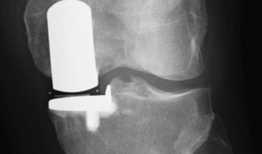

你有没有想过,当你的膝关节像老化的弹簧一样“嘎吱嘎吱”作响时,会有一种神奇的手术能把它换成一个全新的呢?没错,就是膝关节置换手术...